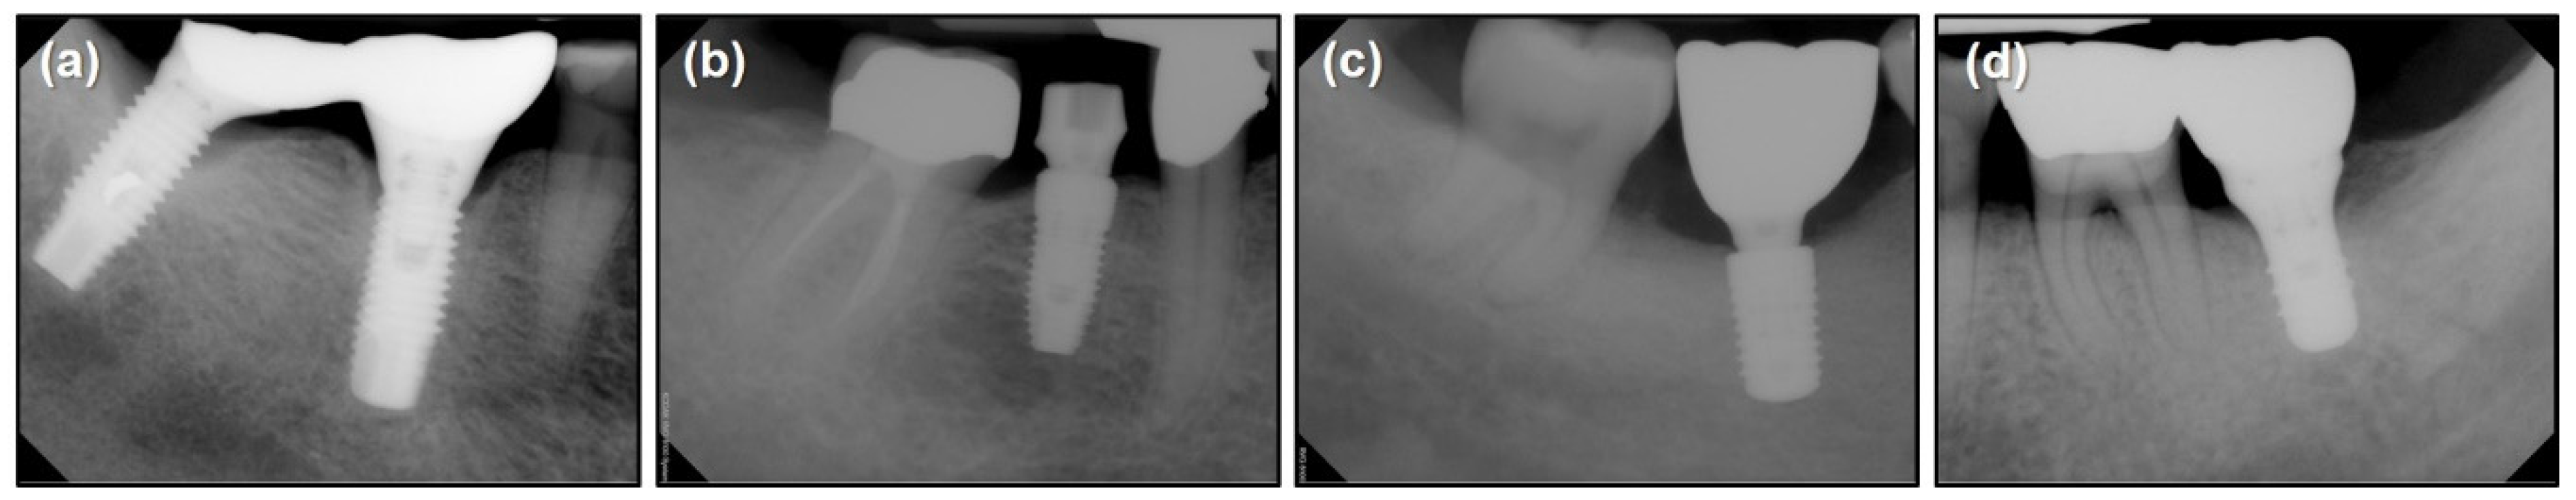

2.2. Materials